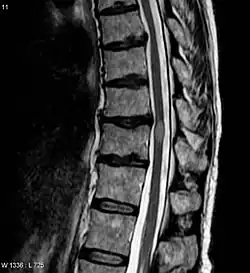

An MRI showing a transverse myelitis lesion, which is lighter, oval shape at center-right. The patient recovered 3 months later.